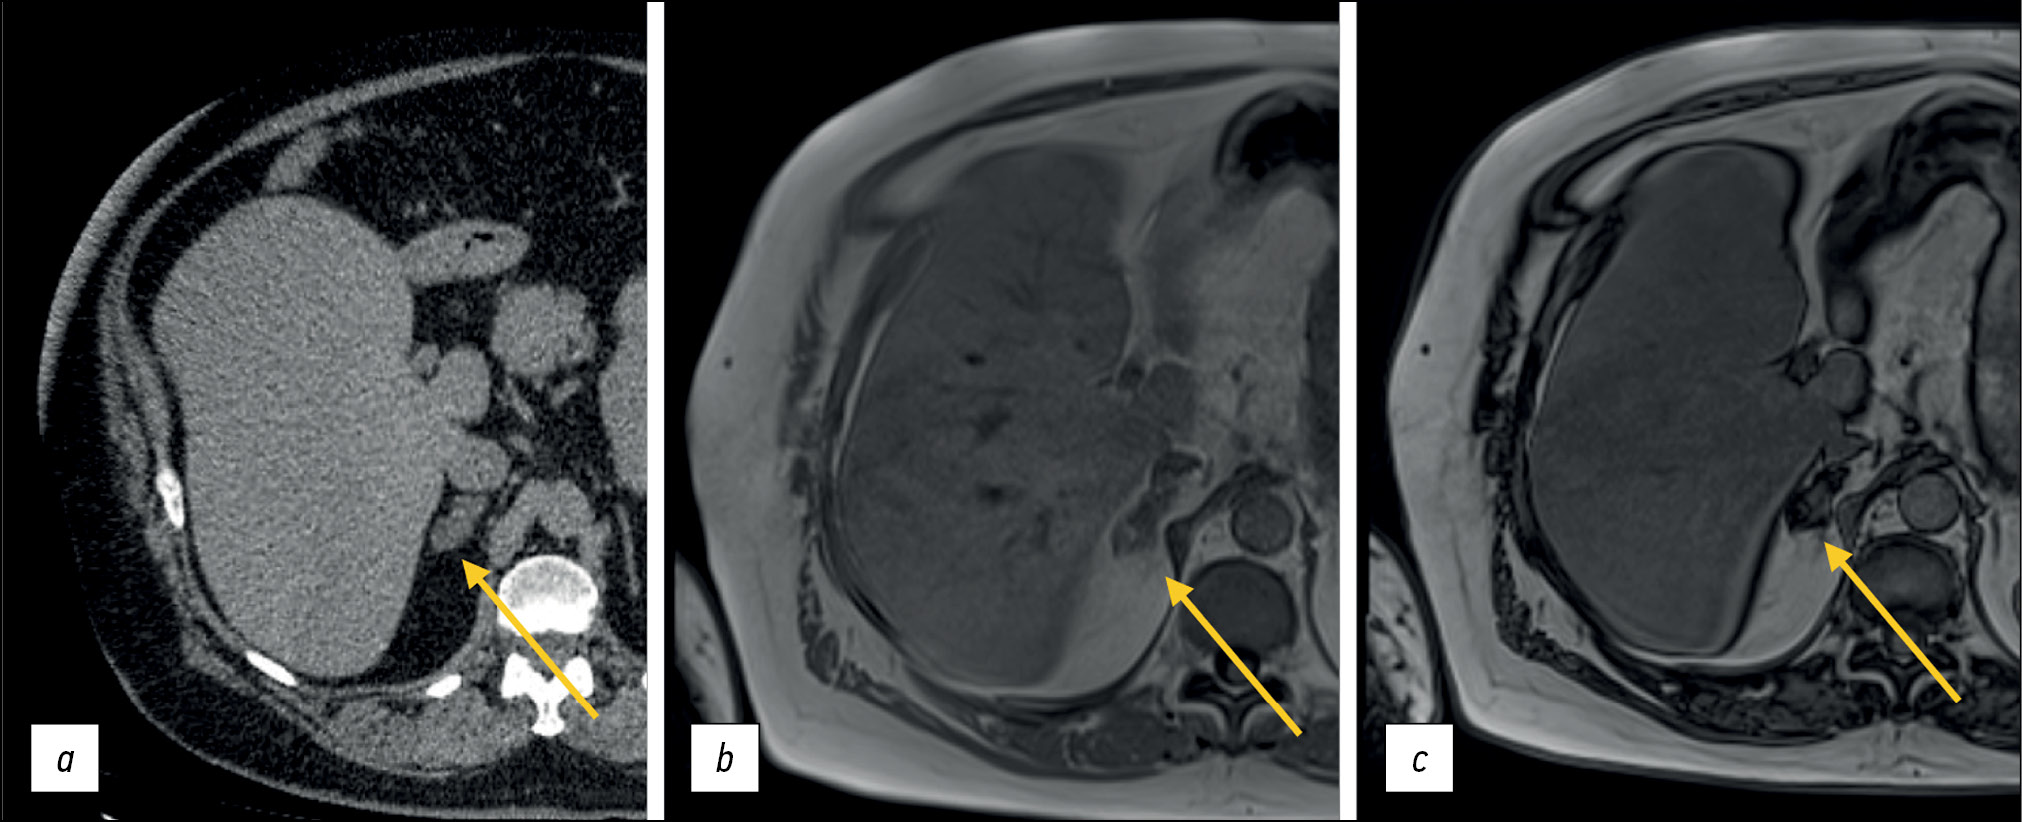

For a more accurate assessment of hepatic steatosis or signs of hemochromatosis, in-phase and opposed-phase T1-WIs should also be included in the standard MRI protocol. Furthermore, this sequence is useful in the diagnosis of adrenal adenoma (Fig. 6), clear-cell renal cell carcinoma, and pancreatic fatty infiltration (Fig. 7). These sequences must be obtained before contrast agent injection. Out-of-phase images allow for the assessment of signal loss from adipose tissue and fat-containing lesions such as liver adenomas or hepatocellular carcinoma. Moreover, the determination of the proton density fat fraction is the gold standard for noninvasive quantitative assessment of hepatic steatosis. However, this sequence is not included in the routine protocol.

Figure 6. Abdominal computed tomography, axial plane (а): a right adrenal mass of nonuniform density is visualized (arrow); abdominal magnetic resonance imaging (b, с), in-phase (b) and opposed-phase (с): a typical signal loss from the adenoma fat component in the opposed-phase is detected (arrows).

Figure 7. Abdominal magnetic resonance imaging, pancreatic lipomatosis (arrows): а in-phase, b opposed-phase. In the opposite phase, a signal loss from the pancreas with a normal signal from the liver is detected.